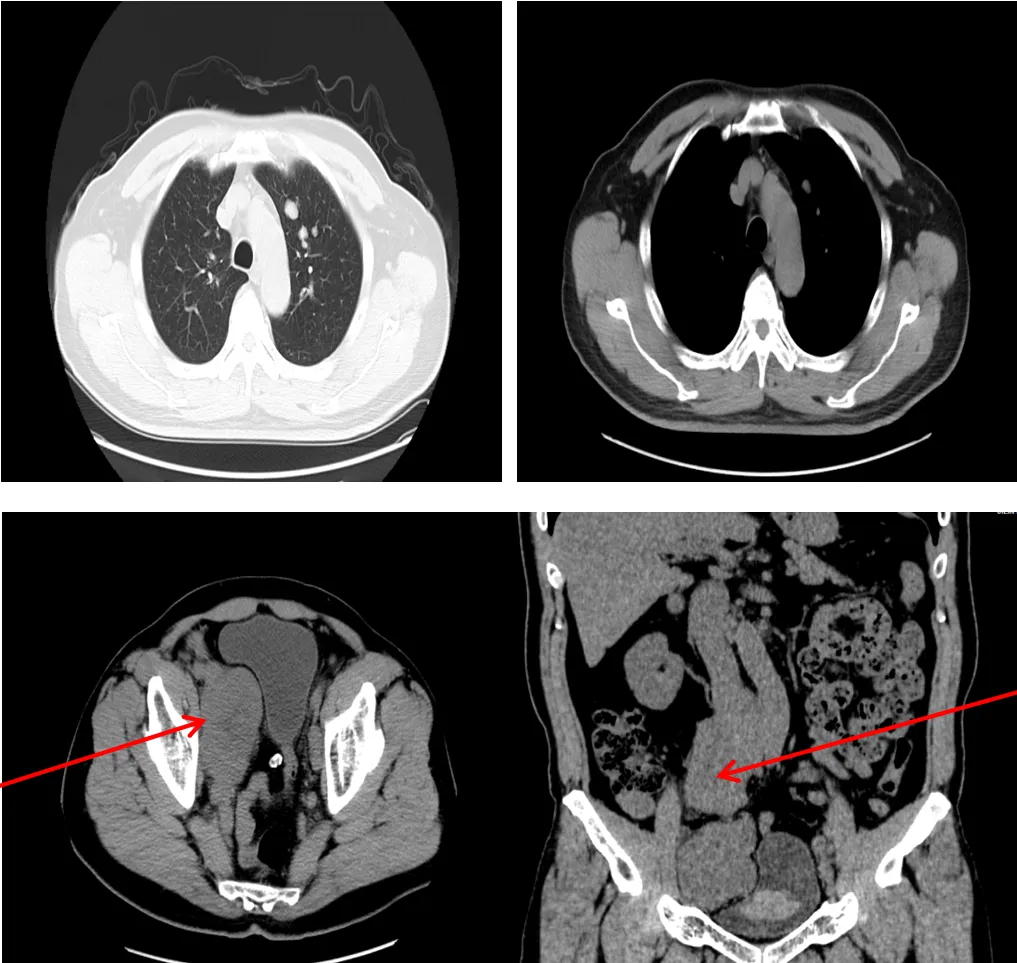

CT影像学检查(2025-08-13)

• 胸部CT:

肺(平扫):与2025-02-06前片对比,双肺多发实性结节较前明显减小,部分消失,提示转移瘤。

• 腹部及盆腔CT:

与2025-02-06双肾+输尿管CT平扫对比:前列腺较前明显减小及双侧精囊腺改变,腹主动脉及双侧髂动脉旁多发肿大淋巴结较前明显减小。

病情治疗效果良好,继续目前治疗。